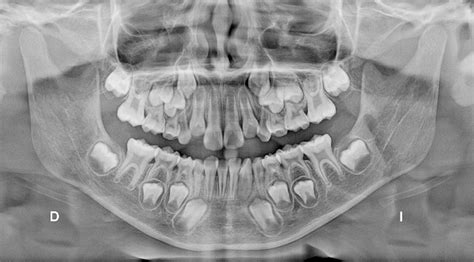

Ejemplo de mamelones dentales en incisivos.